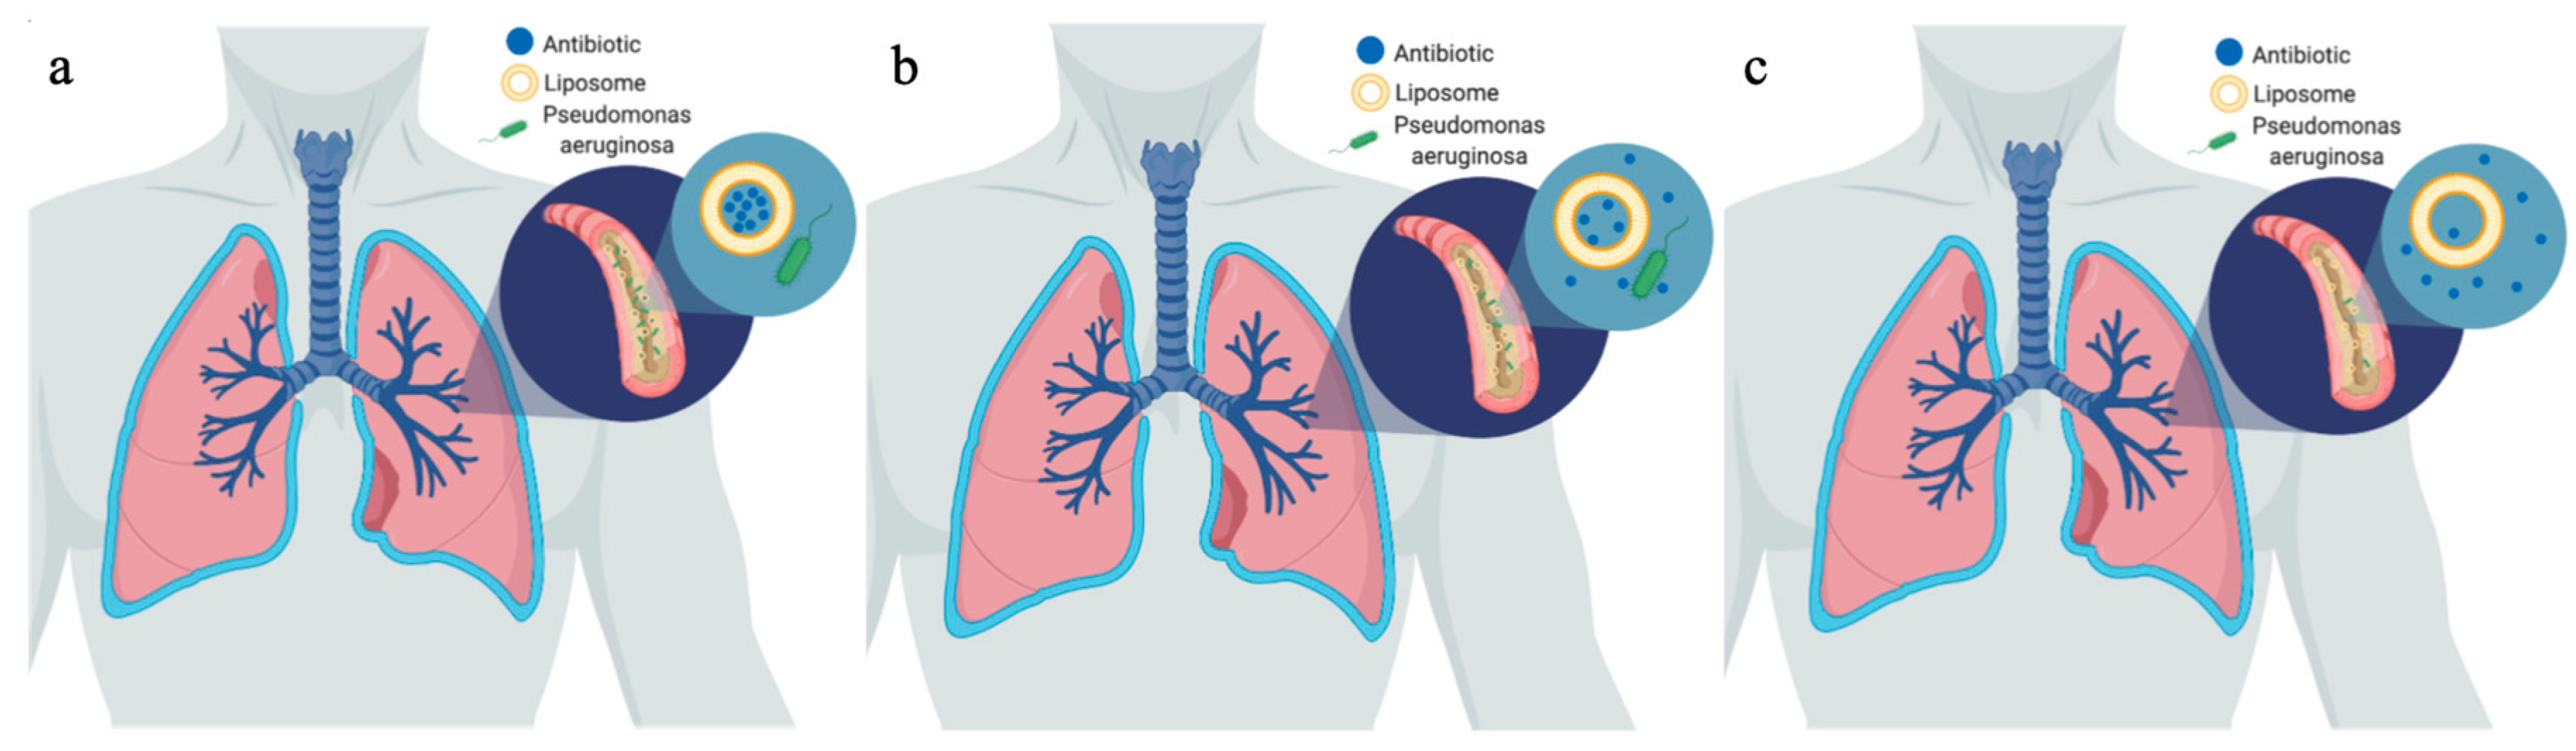

2. Inorganic Nanoparticles